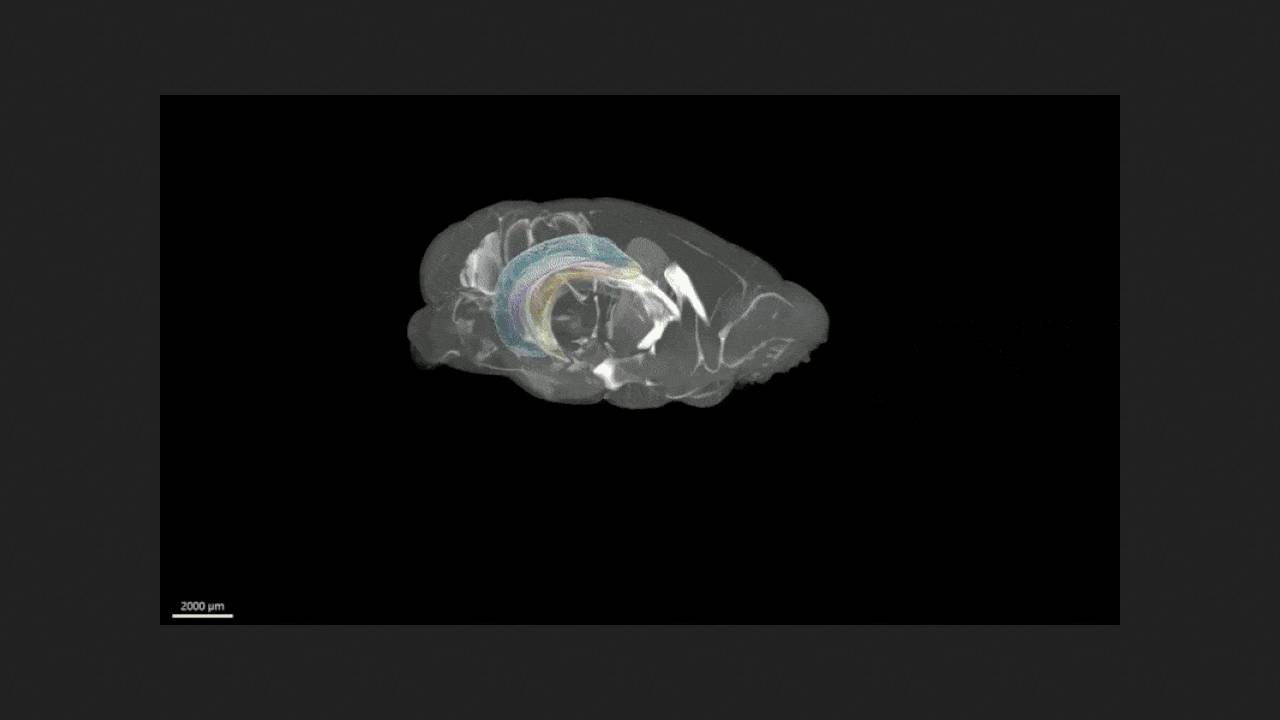

Аллан Джонсон (Allan Johnson) из Дьюкского университета с коллегами представил трехмерный стереотаксический атлас мозга мыши, охватывающий анатомические структуры и клетки. Для его создания мозг и череп пяти мышей визуализировали тремя способами. Сначала мозг в черепной коробке трехмерно визуализировали диффузно-тензорной томографией с разрешением 15 микрометров (в 2,4 миллиона раз выше, чем у клинических томографов), которое позволяет рассмотреть цитоархитектуру мозговых структур. Затем с помощью микрокомпьютерной томографии отметили опорные точки черепа. После этого мозг извлекли и сделали снимки его срезов микроскопией плоскостного освещения, чтобы получить карты клеток. Результаты работы опубликованы в журнале Science Advances.

Данные всех методов визуализации мозга и черепа пяти животных усреднили, скорректировали геометрические искажения и интегрировали в трехмерный атлас, снабдив все структуры метками. Он призван облегчить структурные и функциональные нейробиологические исследования, проводимые на мышином мозге, а также предоставить наглядный материал для обучения студентов. Атлас DMBA объемом около 13 терабайт доступен бесплатно по запросу.